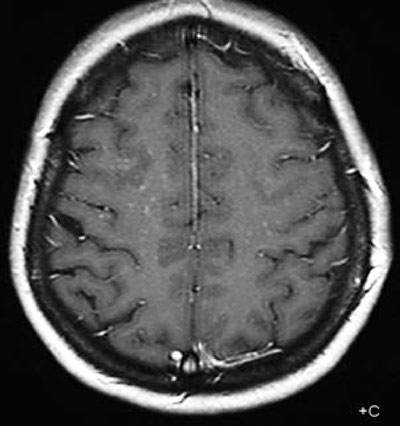

Figure 2

Axial T1 with contrast showing multiple discrete curvilinear lesions in the cerebral white matter of the superior frontal and prerolandic gyrus in both hemispheres.